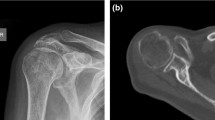

Table 1 demonstrates the results of evaluation of degenerative and trauma shoulders (4-part or Neer Type VI dislocated proximal humerus fractures). The Walch classification, which uses 2-dimensional (2D) axial computed tomography (CT) scans, assesses the glenoid and the position of the humeral head in relation to the glenoid in various degrees of osteoarthritis (Figs. 1, 2). Grade D in sample D2 indicates very severe arthritis with subluxation of the anterior humeral head, grade A1 in sample F2 indicates a well-centered humeral head with minor erosions.

The Hamada classification evaluates the radiological findings after a rotator cuff tear and shows the course of the rotator cuff tear arthropathies (from 1 to 5). Of the trauma specimens, F2 was rated IV/b and orthopedic specimens D1 and D2 were rated IV/a and V, respectively, indicating a poorer prognosis of arthropathy for the orthopedic patients.

The Outerbridge classification is originally based on arthroscopic findings, but in our study, we used MRI scans as an advanced imaging tool; Outerbridge 2 in the case of sample D1 indicates blistering swelling/fraying of the articular cartilage extending to the surface, a moderately damaged cartilage.

Meanwhile, the osteoarthritis score clearly demonstrated the presence of advanced osteoarthritis among the orthopedic indication specimens. In case of control samples, healthy tissue structure was confirmed by histological examination (Fig. 3).